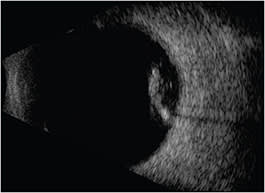

We routinely perform preoperative B-scan and ultrasound biomicroscopy (UBM) to evaluate vitreous traction and lens placement, especially in cases in which corneal edema limits the view, or lens placement is a concern (Figure 1).

Figure 1. Ultrasound biomicroscopy showing a centered IOL in the posterior chamber.